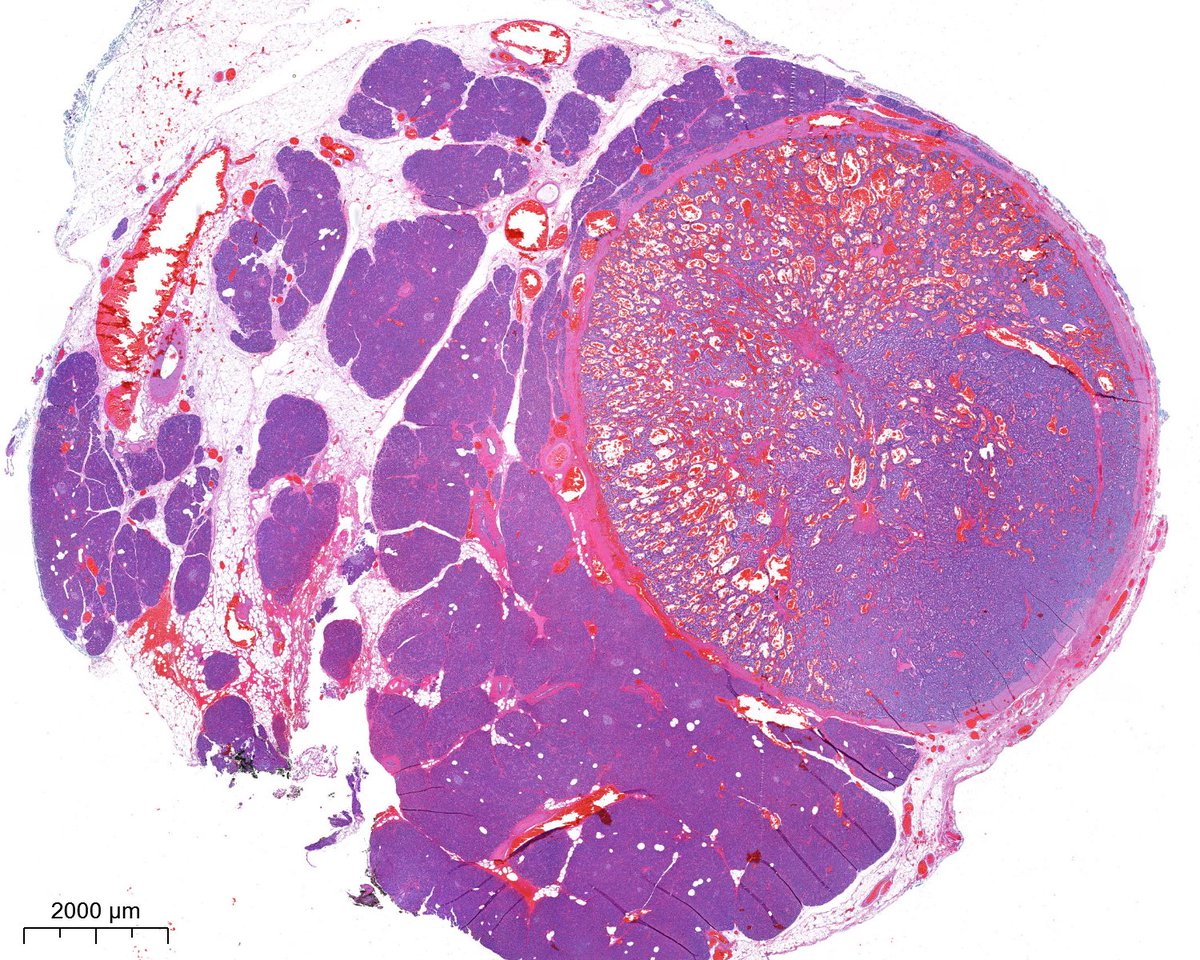

M/60s, 2.2cm well circumscribed soft tissue mass found during workup of L shoulder rotator cuff tear. Mass remained grossly stable for years. Patient is otherwise asymptomatic. #cytopath #histology #PathTwitter #pathology #MedTwitter

USFpathology's tweet image. M/60s, 2.2cm well circumscribed soft tissue mass found during workup of L shoulder rotator cuff tear. Mass remained grossly stable for years. Patient is otherwise asymptomatic. #cytopath #histology #PathTwitter #pathology #MedTwitter

Nice cyto w/u and Dx of schwannoma from @USFpathology #Pathosomes #TwitterPath #Cytology #Neuropath